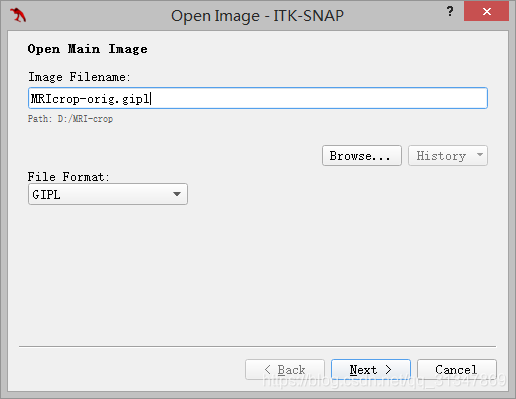

选择图像 MRIcrop-orig.gipl:

SNAP 会根据加载的文件扩展名自动选择格式,但还是要检查一下它选的对不对。

注意:路径中不能包含中文,否则会报错。